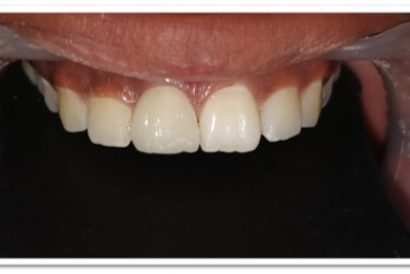

Before

After